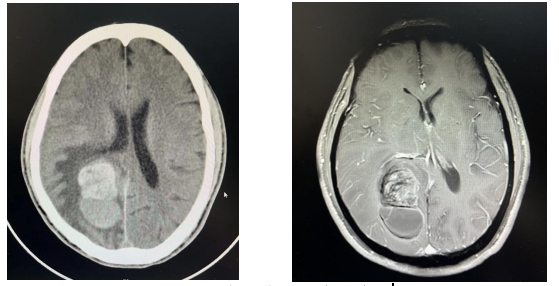

为进一步明确病变性质,神经外科的医生进行了更为详细的检查,颅脑增强MR结果提示:不排除转移瘤可能。也就是头颅内的肿瘤是别的地方转移过来的。

左下角异常部分为肿瘤